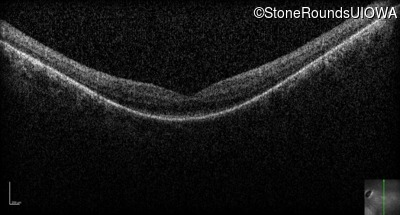

Optical Coherence Tomography - Left - 20/100

Exemplar / OCT Stack

OCT Stack